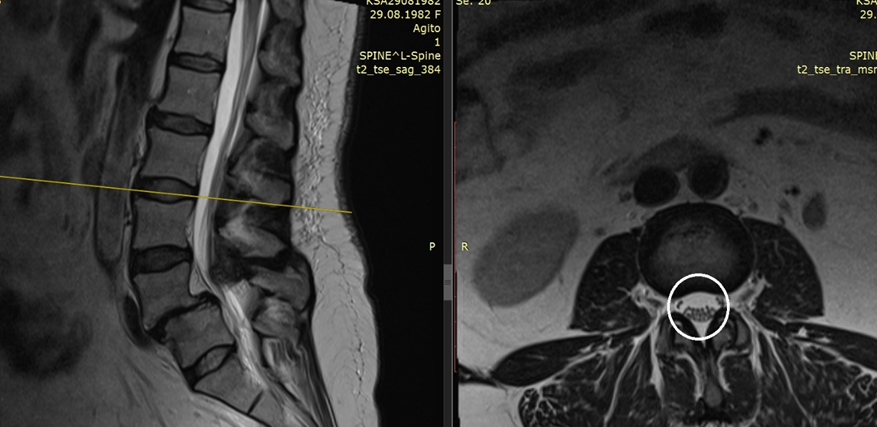

Узость позвоночного канала на фоне листеза вследствии спондилолиза - обведено белым кругом

К сожалению, у вас давний разрыв позвонка на две части, и верхняя часть сползла вперед и перекрыла позвоночный канал – это называется спондилолистез на фоне спондилолиза.

Но теперь, когда позвонок сполз и сформировалась узость позвоночного канала, причем клинически значимая с синдромом «нейрогенной перемежающейся хромоты» - надо оперировать. От консервативного лечения лучше не будет.